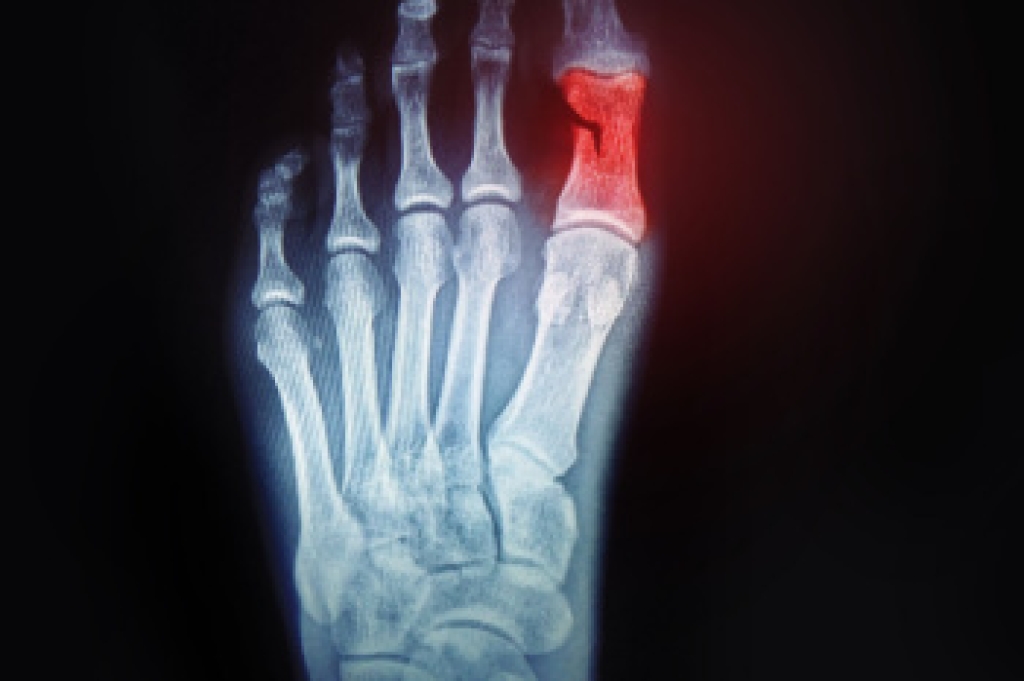

In many cases the cause of toe pain is obvious, but in others, a podiatrist may want to use more advanced methods to determine the problem. These can range from simple visual inspections and sensation tests to X-rays and MRI scans. Prior medical history, family medical history, and any recent physical traumatic events will all be taken into consideration for a proper diagnosis.

Treatments for toe pain and injuries vary and may include shoe inserts, padding, taping, medicines, injections, and in some cases, surgery. If you believe that you have broken a toe, please see a podiatrist as soon as possible.